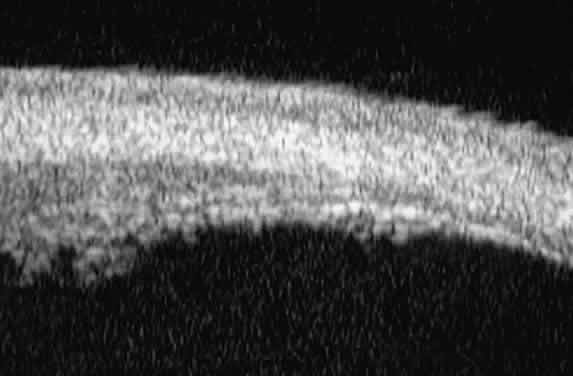

Radial, cross-sectional slices through the posterior ciliary body (Fig. 5) show the sclera as a highly reflective structure that can be easily differentiated from the underlying uveal and neuroepithelial layers of the pars plana. In most patients, UBM is not able to image the ora serrata, peripheral choroid, and peripheral retina.

Fig. 5. Radial UBM slice through pars plana of normal eye.